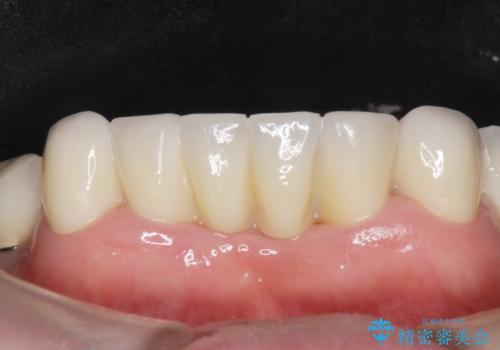

自然な仕上がりと使い心地に喜んで頂けました。

奥歯の治療もやりたいとおっしゃって下さり、今後進めていく予定です。

~被せ物の種類~

ジルコニアクラウン スタンダード

- ¥1,010,000 (仮歯×9本、ファイバーコア×1本、ジルコニアクラウン スタンダード×9本)費用は治療当時の料金となります